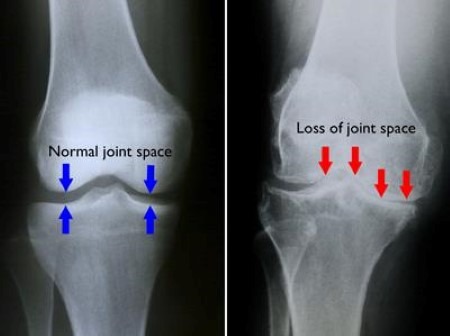

Osteoarthritis is the most common type. It happens when cartilage wears down over time. It is often linked to aging but can also affect younger people especially after injury or heavy joint use.

Imaging tests such as X rays MRI or ultrasound may be used to see joint damage or inflammation.

Accurate diagnosis is important because treatment depends on the specific type of attrities.